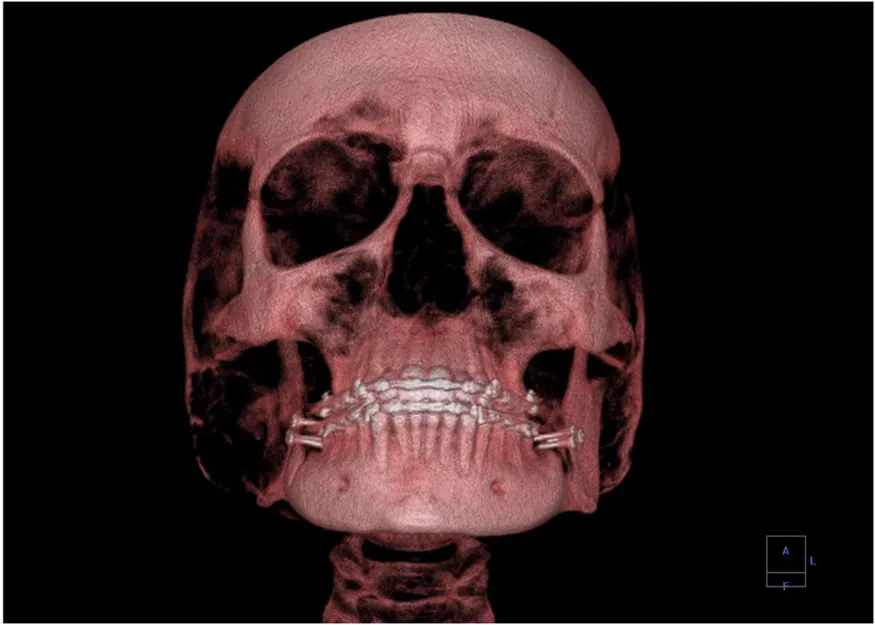

A 3-D image showing a human skull from the front.

Figure 30.26 This three-dimensional image of a skull was produced by computed tomography, involving analysis of several x-ray slices of the head. (credit: Emailshankar, Wikimedia Commons)

A standard x ray gives only a two-dimensional view of the object. Dense bones might hide images of soft tissue or organs. If you took another x ray from the side of the person (the first one being from the front), you would gain additional information. While shadow images are sufficient in many applications, far more sophisticated images can be produced with modern technology. Figure 30.25 shows the use of a computed tomography (CT) scanner, also called computed axial tomography (CAT) scanner. X rays are passed through a narrow section (called a slice) of the patient’s body (or body part) over a range of directions. An array of many detectors on the other side of the patient registers the x rays. The system is then rotated around the patient and another image is taken, and so on. The x-ray tube and detector array are mechanically attached and so rotate together. Complex computer image processing of the relative absorption of the x rays along different directions produces a highly-detailed image. Different slices are taken as the patient moves through the scanner on a table. Multiple images of different slices can also be computer analyzed to produce three-dimensional information, sometimes enhancing specific types of tissue, as shown in Figure 30.26. G. Hounsfield (UK) and A. Cormack (US) won the Nobel Prize in Medicine in 1979 for their development of computed tomography.